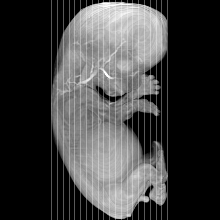

Human Embryo

Carnegie Stage 23 (56 post-ovulatory days)

Most embryos at stage 23 are approximately 56-57 postovulatory days old and measure 23-32 mm in length. Distinguishing criteria for this stage include fusion of the eyelids at the medial and lateral margins, clear distinction of the subdivisions of the upper and lower limbs, the forearms appear at or above the level of the shoulders, the superficial vascular plexus of the head is very close to the vertex, and the external genitalia are well developed but not always sufficiently to distinguish the embryo's sex.

(NOTE: These specimens are late stage 23.)

MRI Slice Selector